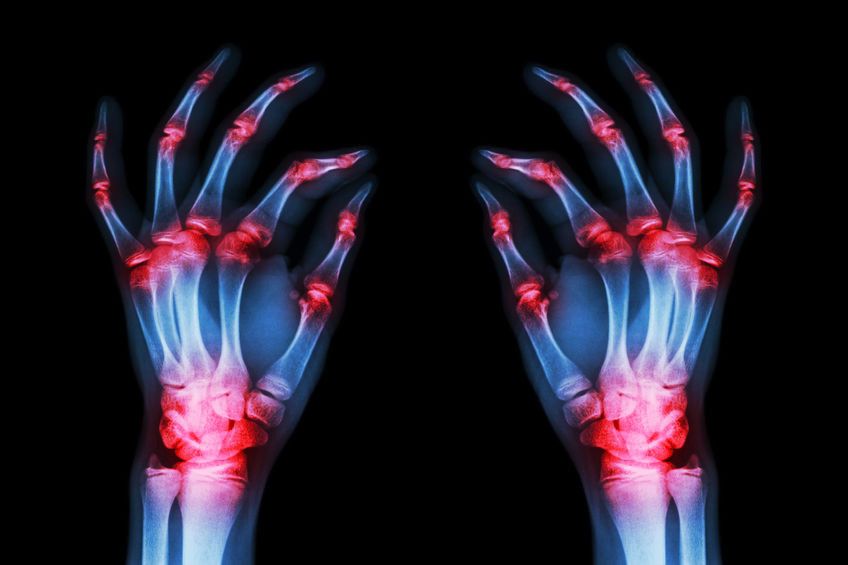

- Reumatoid artritisReumatoid artritis merupakan penyakit autoimun. Ini adalah kondisi dimana sistem kekebalan tubuh ‘menyalahartikan’ jaringan yang sehat sebagai ancaman bagi tubuh dan menyerangnya.Pada reumatoid artritis, terjadi peradangan yang merusak sendi, pembuluh darah, dan organ tubuh lainnya. Nyeri sendi biasanya dialami pada beberapa persendian seperti tangan, kaki dan pergelangan tangan. Nyeri umumnya juga disertai dengan pembengkakan sendi dan sulit menggerakkan persendian.

- OsteoartritisPada osteoartritis terjadi peradangan di membran synovial, yaitu membran yang menyelubungi dan melindungi sendi sehingga sendi dapat bergerak bebas. Jika membran sinovial meradang, maka terjadi pembengkakan, nyeri, dan kaku sendi. Sendi yang terkena biasanya pada jari– jari tangan, pinggul, dan lutut.